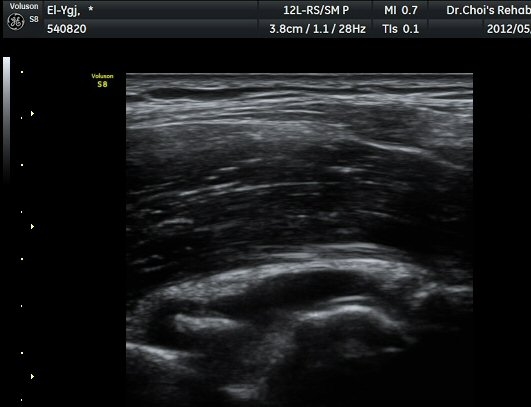

ÁÖ°ü Ⱦ´Ü¸é°Ë»ç¿¡¼­ °üÀý³» ¼ö¾×Àú·ù¿Í ô°ñ½Å°æÀÇ Ç¥ÃþÀ¸·Î ÀüÀ§°¡ °üÂûµÈ´Ù(±×¸² 7).

ÁÖµÎ¿Í È¾´Ü¸é°Ë»ç ¿µ»ó¿¡¼­(»çÁø) ÃÊÀ½ÆÄ À¯µµÇÏ¿¡ °üÀý³» Áֻ縦 ½ÃÇàÇÏ¿´´Ù(µ¿¿µ»ó).